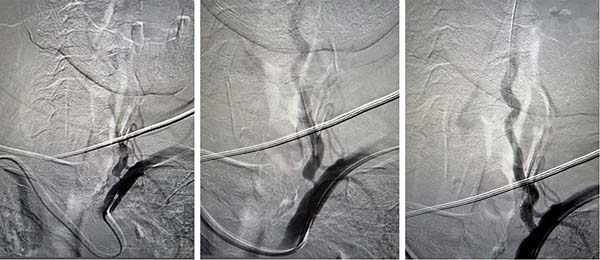

经桡动脉脑血管介入技术具有创伤小、恢复快、并发症少、患者舒适度高等优势,尤其适用于高龄、卧床耐受差或合并排尿障碍的患者。术中脑血管造影显示,患者左侧椎动脉次全闭塞。手术团队通过悬吊及超选择性微导丝悬吊技术,成功将支架精准植入左侧椎动脉狭窄段。术后造影显示患者后循环血流恢复通畅,灌注明显改善,手术过程顺利。

左侧椎动脉植入支架后狭窄显著改善